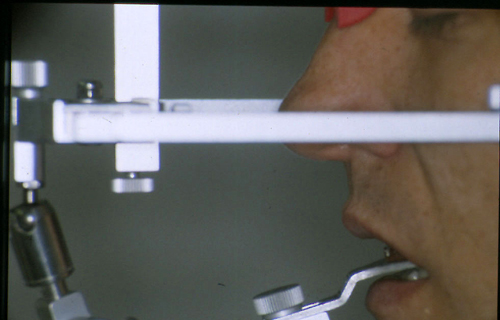

ABSTRACT El Bruxismo es una entidad patológica en la que concurren diferentes factores. Entre ellos el stress que conlleva consigo la vida moderna, constituye el Factor Predisponente sobre el que se ha abundado en innumerables tratamientos de tipo general, actuando sobre la psiquis y el comportamiento del individuo, ya sea con fármacos o bien mediante medios psicológicos. Sin embargo, como tantos desequilibrios provocados por el stress, confluyen siempre con un Factor Desencadenante, que en el caso del Bruxismo se encuentra en las desarmonías entre los componentes varios del Sistema Estomatognático. DESARROLLO Paciente varón, de 43 años, constitución atlética. A la inspección se observan desgastes oclusales que alcanzan la calidad de Facetas Parafuncionales, con dentina expuesta y empastes totalmente gastados y evidentes signos de falta de Disclusión Canina de ambos lados. Sobre dicho montaje se realiza un Encerado Progresivo de Diagnóstico, aportando en el mismo los elementos necesarios para obtener todos los principios básicos de una Oclusión Orgánica. FIG. 6 a 24 Una vez aprobado el fisiologismo de la oclusión en el articulador, se reproducen modelos de yeso con la nueva situación, y se estampa un SET UP en cada maxilar. FIG. 25/26 Procedemos entonces al tallado de las piezas correspondientes a la Guía Anterior, y rebasamos los estampados, creando en boca una nueva situación desoclusiva, que permanece en boca durante los pocos días que transcurren entre la primera y segunda visita de trabajo. FIG. 27/33 Ya abordando en esta segunda visita los sectores posteriores, tanto superiores como inferiores, tallamos siempre de manera supragingival, destacando la importancia vital de la forma obtenida en las provisionales, a las que abrimos plenamente las troneras para lograr una correcta higiene. FIG.34 a 43 FIG. 44 a 52 Efectuados los colados en oro y probados en boca, en el laboratorio se confecciona el bizcochado de la nueva Guía Anterior, la que puede o no copiarse de la Guía Anterior provisional, mediante la técnica denominada Trayectoria Funcionalmente Generada, que consiste en realizar en la platina del articulador un registro estereográfico sobre acrílico Duralay en polimerización. FIG. 57/58 Ajustados todos los detalles mediante esta técnica, se instala en boca en forma Provisional y se deja funcionando una semana o dos, al cabo de las cuales se chequean las disclusiones , los ajustes, la eficacia masticatoria, la carencia de sintomatología articular y muscular. FIG.59 a 63 PIE DE FOTO FIG.9 OBTENCIÓN DE LA GUÍA ANTERIOR FIG.10 Y 11 PITOMBOS. ALINEAC. TRIDIMENSIONAL FIG.12 PITOMBOS. DISCLUSIÓN DER. FIG.13 PITOMBOS. DISCLUSIÓN IZQ. FIG.14 WILSON INF. FIG.15 WILSON SUP. FIG.16 BOCA DE PEZ INF. FIG.17 BOCA DE PEZ SUP. FIG.18 VISTA OCLUSAL FIG.19 O.R.C. FIG.20 DISCLUSIÓN DERECHA FIG.21 CRESTAS TRIANG. INT. FIG.22 CRESTAS TRIANG. INT. FIG.23 CRESTAS TRIANG. INT. FIG 24 CRESTAS TRIANG. INT. FIG.59 DISCLUSIÓN IZQ. FIG.60 DISCLUSION IZQ. FIG.61 DISCLUSIÓN DER. FIG.62 DISCLUSION DER. FIG. 63 AJUSTE PERIFÉRICO

Se nos hace evidente la necesidad de proceder a rehabilitar todo el sistema, y se programa el correspondiente estudio oclusal, mediante un montaje en articulador semiajustable, el que se realiza luego de dos semanas de uso de una Férula de Desprogramación.